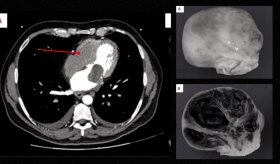

Los mixofibrosarcomas del corazón son tumores extremadamente raros, agresivos y de mal pronóstico, frecuentemente diagnosticados de manera tardía debido a síntomas inespecíficos.